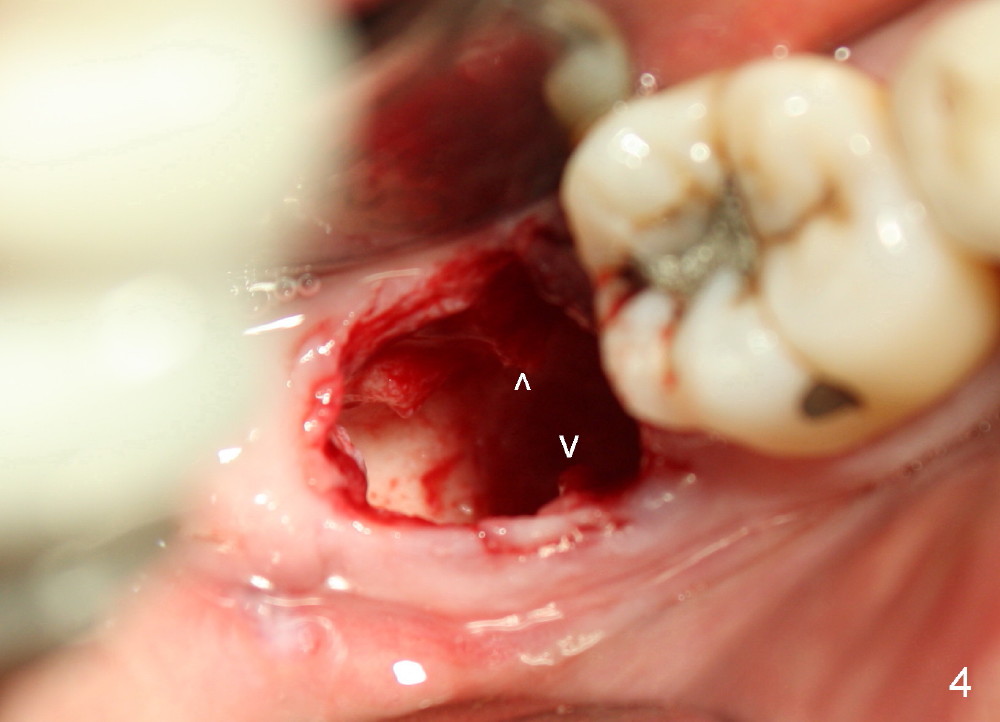

The gingiva forms a band (cuff) around the implant (Fig.11 *) and bone has apparently filled the peri-implant gap (Fig.13 *) 3.5 months postop. The gingival cuff is present immediately pre-crown cementation (Fig.12 *). The bone density around the implant continues to increase 2 and 7 months post cementation (Fig.14,15), in spite of retention of residual cement distally (<).